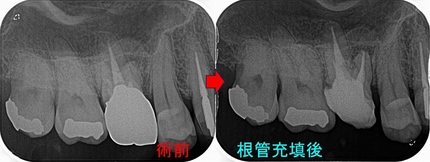

過去に抜髄をしているようですが、4根管中1根(口蓋根)しか治療していない感じ

治療は2回で仕上げました。

病変の原因と思われる、MB,MB2もガッタパーチャー使用